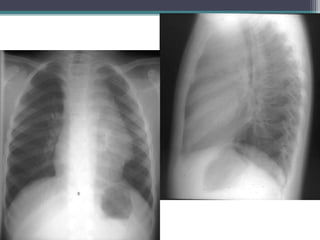

Three year old male with an

incidentally noted chest

mass

โ–ซ Single slice from an enhanced chest CT exam shows the mass to be

non-enhancing, posterior to the right bronchi, and next to the

esophagus.

โ–ซ Dx: Esophageal Duplication